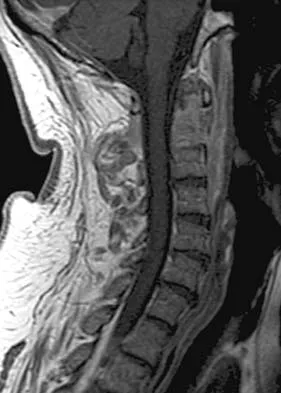

Figures 5a and 5b show the radiograph and MRI scan of a patient who has severe mechanical neck pain but no neurologic problems. Biopsy and work-up show the lesion to be a solitary plasmacytoma. Treatment should consist of

Explanation

Plasmacytoma is very sensitive to radiation therapy and given the complexity of the resection and complications of surgery in the given location, radiation therapy is preferred. However, the patient has clear loss of bony structural integrity, and resultant instability would persist even with tumor irradiation; therefore, posterior stabilization is warranted. Chemotherapy and bone marrow transplant are reserved for systemic disease with multiple myeloma. Corwin J, Lindberg RD: Solitary plasmacytoma of bone vs. extramedullary plasmacytoma and their relationship to multiple myeloma. Cancer 1979;43:1007-1013.